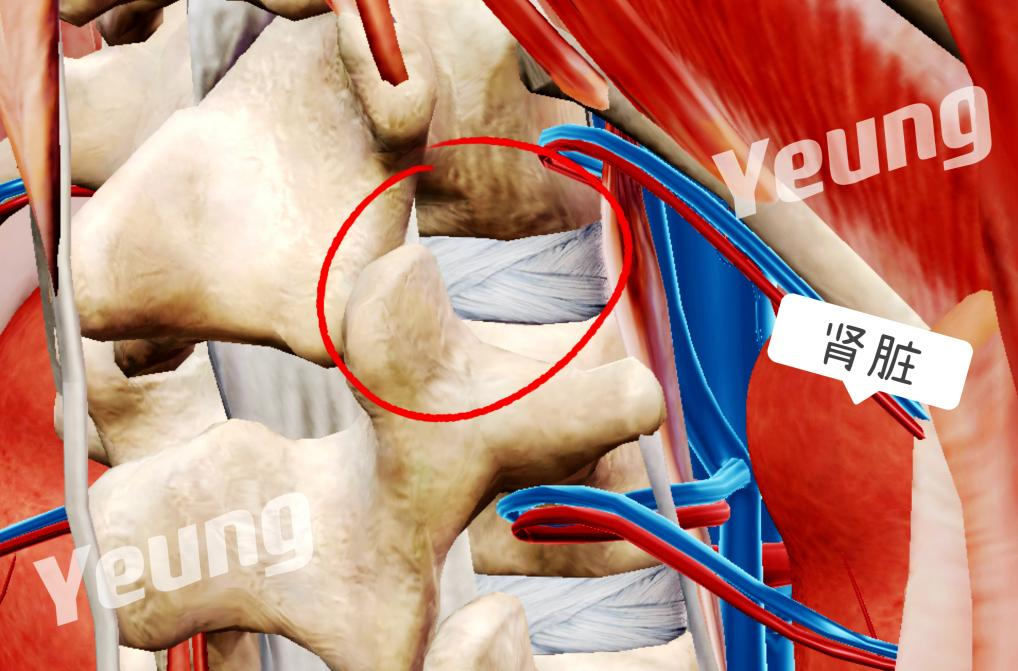

脊柱病医院院长郝定均及脊柱病医院腰椎病区主任刘团江查房后,提出患者手术指征明确,但不能耐受开刀手术,建议采用微创手术治疗。同时需要特别注意手术位置临近脊髓圆锥和肾脏,手术风险较大,术中一定要注意脊髓神经功能和脏器保护。

解剖示意图